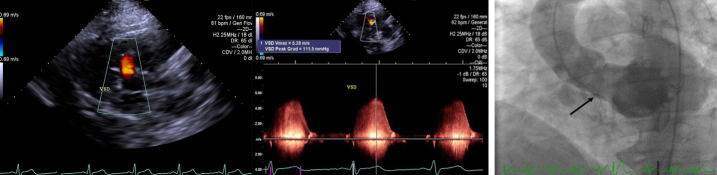

室间隔缺损(VSD)是当今世界上最常见的先天性心脏病之一。虽然大多数是自发关闭,经导管室间隔关闭是一种常见的选择,有症状的患者在成年合适的解剖结构。虽然经食管超声心动图(TEE)和心内超声心动图是该手术最常见的成像方式,但在TEE图像不佳的患者中,经胸超声心动图(TTE)可作为可靠的替代方法。在这里,我们报告了一例肺动脉高压合并肌肉性室间隔缺损的成年患者,由于TEE图像不佳,经皮采用二维TTE缝合。

Ventricular septal defect (VSD) is one of the most common congenital heart diseases worldwide today. Although the majority close spontaneously, transcatheter VSD closure is a common option for symptomatic patients with suitable anatomy in adult age. Although transesophageal echocardiography (TEE) and intracardiac echocardiography are the most common imaging modalities for the procedure, in patients with poor TEE images, Transthoracic echocardiography (TTE) can be used as a reliable alternative. Here we present an adult patient with pulmonary hypertension associated with a muscular VSD which was closed percutaneously using 2-dimensional TTE because of poor TEE images.